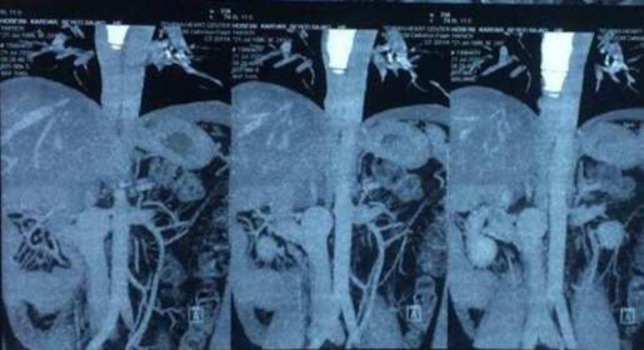

Case presentation: A 23-year-old male with no cardiovascular risk factors or prior cardiovascular disease presented with atrioventricular reentrant tachycardia that converted to sinus rhythm after adenosine administration. The patient was scheduled for an electrophysiology study with catheter ablation if indicated. During the procedure, catheter advancement into the right atrium was unsuccessful, raising suspicion of an interrupted inferior vena cava (IVC). Radiofrequency ablation was subsequently performed successfully via the subclavian vein approach. Post-procedural computed tomography (CT) imaging confirmed interruption of the IVC.